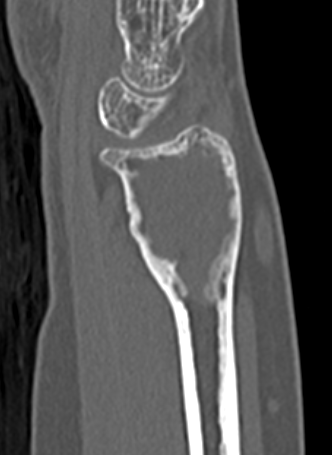

CT

X-ray

Eccentric, sharply demarcated lytic lesion

- no sclerosis around lesion

- narrow zone of transition

- metaphysis, extending into epiphysis

- no mineralization